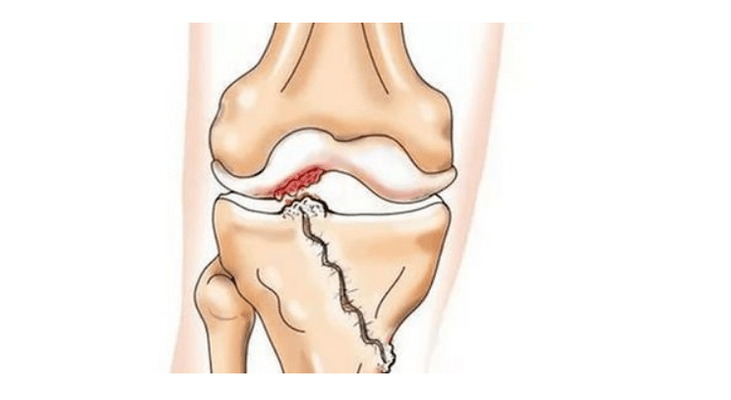

- injuries (fractures, meniscus and anterior cruciate ligament tears).Unfortunately, these injuries put excessive stress on the cartilage in all people, regardless of age.The fracture of any part of the bones covered with cartilage is accompanied by the formation of an unevenness - "step".In this area, wear occurs during movement and arthrosis develops;

During arthrosis (osteoarthrosis), in addition to the progressive destruction of the cartilage, loss of elasticity and shock-absorbing properties, the bones are gradually involved in the process.Under load, sharp edges (exostoses) appear, which are mistakenly considered "salt deposits" - salt deposits do not occur in classic arthrosis.As arthrosis progresses, it continues to "eat away" the cartilage.Then the bone is deformed, cysts are formed, all the structures of the joint are affected, the leg bends.

In the second stage, the cartilage layer thins sharply and is completely absent in some places.Osteophytes appear along the edges of the joint surfaces.The qualitative and quantitative characteristics of synovial fluid of the joint change - it becomes denser, more viscous, which leads to deterioration of its nutritional and lubricating properties.The pain is more prolonged and intense, and a creaking sound is often heard during movement.There is mild or moderate limitation of movement and mild deformation of the joint.Taking pain relievers will help ease the pain.

Gonarthrosis, III

Porchiány in most affected areas, severe sclerosis (hardening) of the bone, many osteophytes and sharp narrowing or absence of the joint space.The pain is almost constant, and walking is impaired.Mobility is sharply limited and joint deformation is noticeable.NSAIDs, physiotherapy and other usual methods of treating knee arthrosis are ineffective.